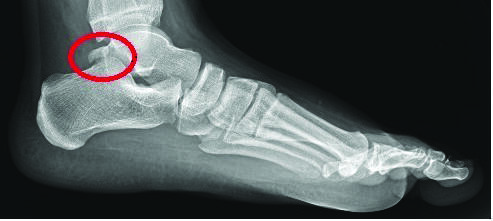

How Could MIS Play a Role for Os Trigonum Syndrome?

A recent review in the American Journal of Sports Medicine takes a closer look at where minimally invasive surgery could apply to patients with a symptomatic os trigonum. The study systematically reviews the effectiveness and safety of minimally invasive surgery (MIS) for treating os trigonum syndrome, a common cause of posterior ankle pain traditionally managed through open excision. Conducted using databases like PubMed and MEDLINE up to February 2023, the review included 17 articles covering 435 patients.1